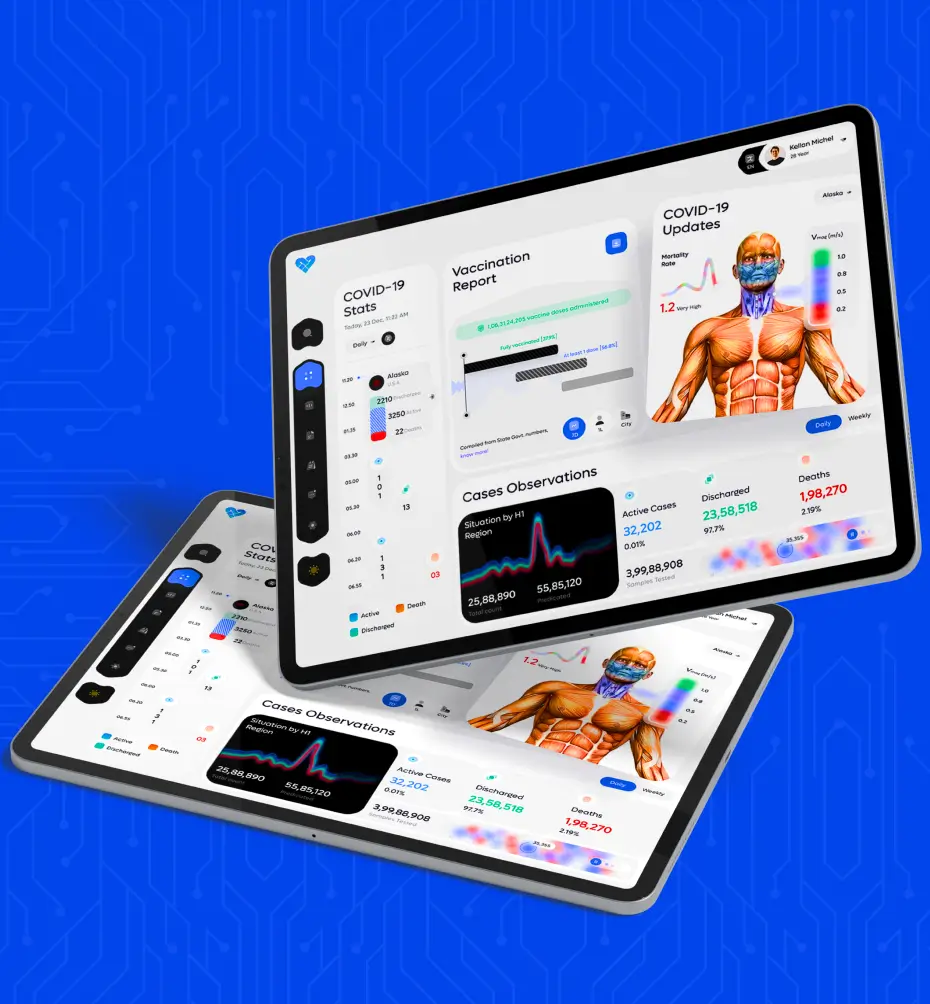

Astarte Medical

Creating software for Astarte Medical involves a meticulous process aimed at addressing their specific needs and objectives. It begins with thorough research and planning to understand the requirements goals of the project.

- Industry: Computer software

- Country: Germany, Issum

CAE Blue Phantom

CAE Blue Phantom is a cutting-edge simulation technology designed to revolutionize medical training and education. Utilizing advanced virtual reality and artificial intelligence, CAE Blue Phantom provides.

- Industry: Wellness & Fitness

- Country: Germany, Issum